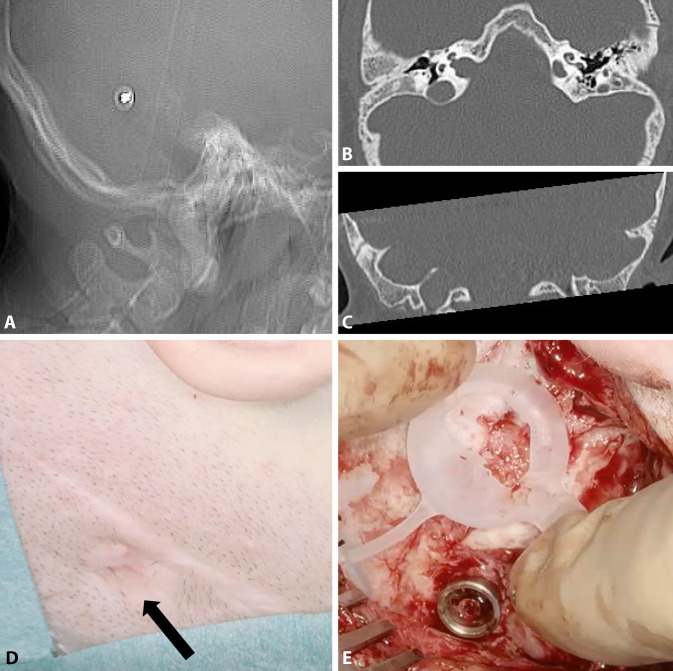

Figure 8 shows the preoperative planning for an adult patient with bilateral complex malformation and after previous hearing rehabilitation with a percutaneous bone conduction hearing implant on the right side (BAHA, Cochlear, Sydney, Australia) and a transcutaneous system on the left side (BCI 601). The patient had experienced recurrent skin irritation around the abutment, including skin overgrowth; therefore, the percutaneous bone conduction system on the right side was replaced with a BCI 602. Detailed preoperative CT-based planning was required due to scars from the previous skin incisions, the plan to simultaneously explant the fixture, and the presence of mastoid hypoplasia. Placing the BC-FMT required limited exposure and temporary impression of the sigmoid sinus (Fig. 9). By pressing the bony island of the sinus inward with a suction tip, it could be protected while the BC-FMT implant bed was molded with the burr. This technique can also be applied to avoid injury to the dura.

Fig. 8.

Radiological planning and surgical field for the simultaneous explantation of a fixture from a percutaneous bone conduction implant and implantation of a BCI 602 (right ear). A The computed tomography (CT) scout view shows the fixture. Axial CT (B) and coronal (C) CT show mastoid hypoplasia, the lateralized sigmoid sinus, and minimal cortical bone thickness (<5 mm) at the bone conduction-floating mass transducer (BC-FMT) position. The abutment is completely overgrown with skin (black arrow) (D) and is removed before creating the implant bed (E). (A–C: CT images reproduced with permission from Prof. Dr. med. M.A. Weber, Institute for Diagnostic and Interventional Radiology, Pediatric and Neuro-Radiology, University Medicine Rostock)